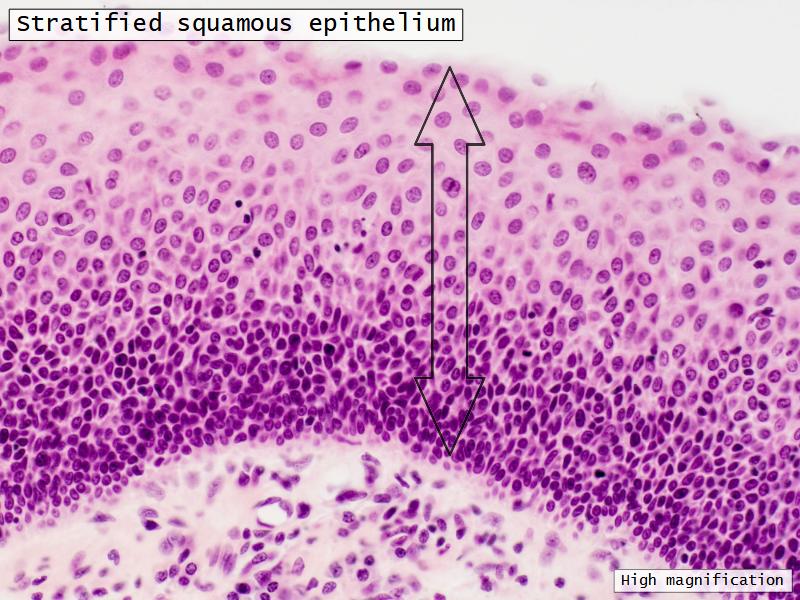

Epiglottis

Respiratory epithelium

- Pseudostratified

- Ciliated

- Columnar

- Epithelium with

- 4 Cells

- Ciliated columnar cells

- Non-ciliated columnar cells

- Goblet cells

- Basal cells